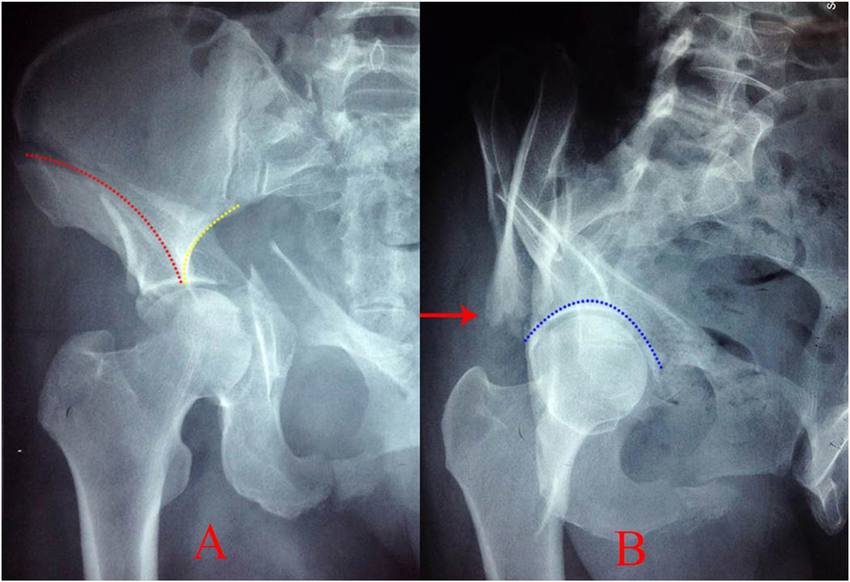

_____ sign is seen in bicolumnar T-shaped or transverse fracture of acetabulum

According to the position assumed by the femoral head, anterior dislocation of the hip can further be classified as _____ and inferior